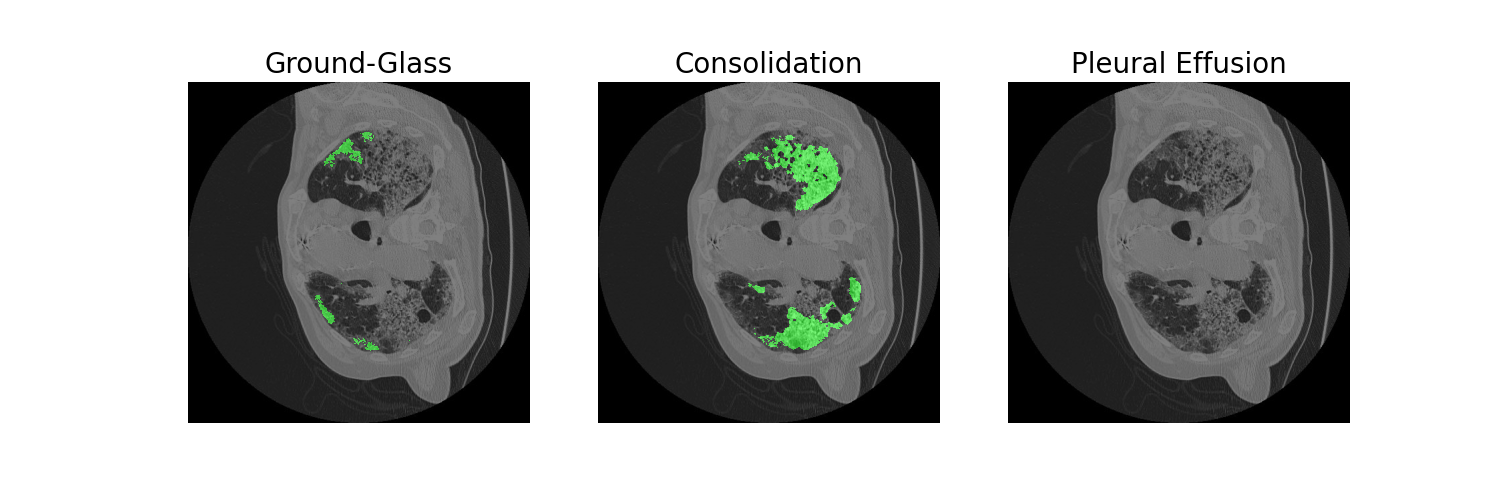

The following is an AI medical segmentation tool for detecting ground-glass, consolidation and pleural effusion in patient lung CT scans. Some reports have shown that ground-glass/consolidation measurements can further enhance the prognosis estimation for Covid-19 patients.

For the front-end, we have used anvil which is a python-based platform to build our very own app. The platform provided us with a mechanism to build a rapid and working prototype of our idea. For our backend-server, we have deployed our deep learning model on a highly reliable AWS server using an EC2 instance. For the deep learning part, we trained a state-of-the-art U-SegNet model for medical segmentation using PyTorch.